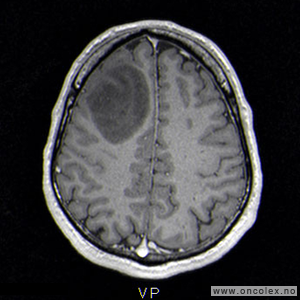

Bildediagnostiske undersøkelser

MR er det viktigste diagnostiske hjelpemiddel for å påvise hjernesvulster. Ofte gjøres det først en CT av hjernen, men CT-undersøkelsen har klare begrensninger når det gjelder fremstilling av hjernesvulster. CT- eller MR-angiografi gjøres av og til for å kartlegge blodåresystemet i hjernen og eventuelle blodårer i og rundt en svulst.

Undersøkelse og kartlegging av aktiviteten i hjernen og områder som styrer de ulike hjernefunksjoner (funksjonell MR), er et viktig supplement i utredningen før operasjon. Dette gjelder spesielt for svulster som ligger i nærheten av områder som styrer språk og motorikk (bevegelse). Måling av hjernens elektriske aktivitet (EEG) og testing for språkfunksjonen i de to hjernehalvdelene (WADA-test) kan også være aktuelt.